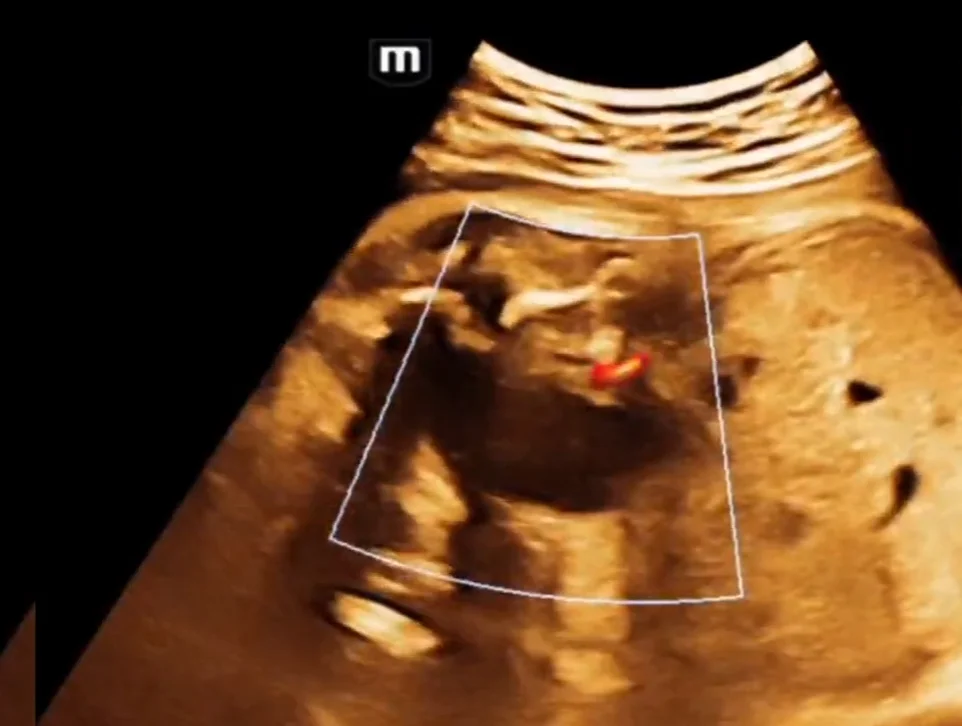

• Van niệu đạo sau ở thai nhi (Posterior Urethral Valves - PUV)

• Hội chứng bụng hình quả mận ở thai (Prune-Belly Syndrome)

• Sa lồi (nang) niệu quản thai nhi (Ureterocele)

• Ống niệu rốn thai nhi (Urachus)